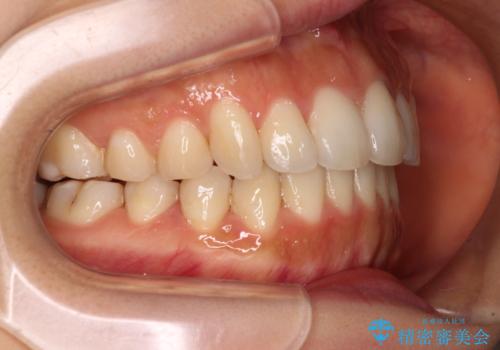

奥歯の咬み合わせを見ると、上顎が下顎に対して相対的に前方にありました。

口元の突出感を改善するためには、上顎臼歯を後方に移動させた咬み合わせにする必要があります。

インビザライン単体で改善することも可能ですが、達成する可能性が高くないため、カリエールディスタライザーという補助装置を併用して、より確実性を上げることとしました。

奥歯の咬み合わせを改善しながら、並行してインビザラインで歯列を整えることとしました。

カリエールディスタライザーを併用したことで、確実かつ短期間で治療を終えることができました。